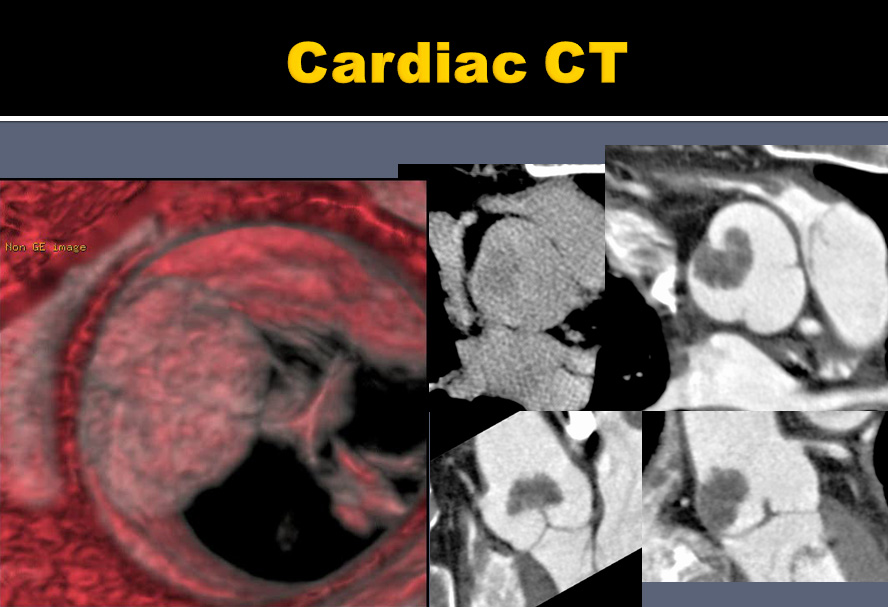

| 55yr / M, Lung cancer, 3 years ago |

Ju Won Lee, Yeon Hyeon Choe |

Sungkyunkwan Univ. Samsung Medical Center (SMC), Seoul, Korea |